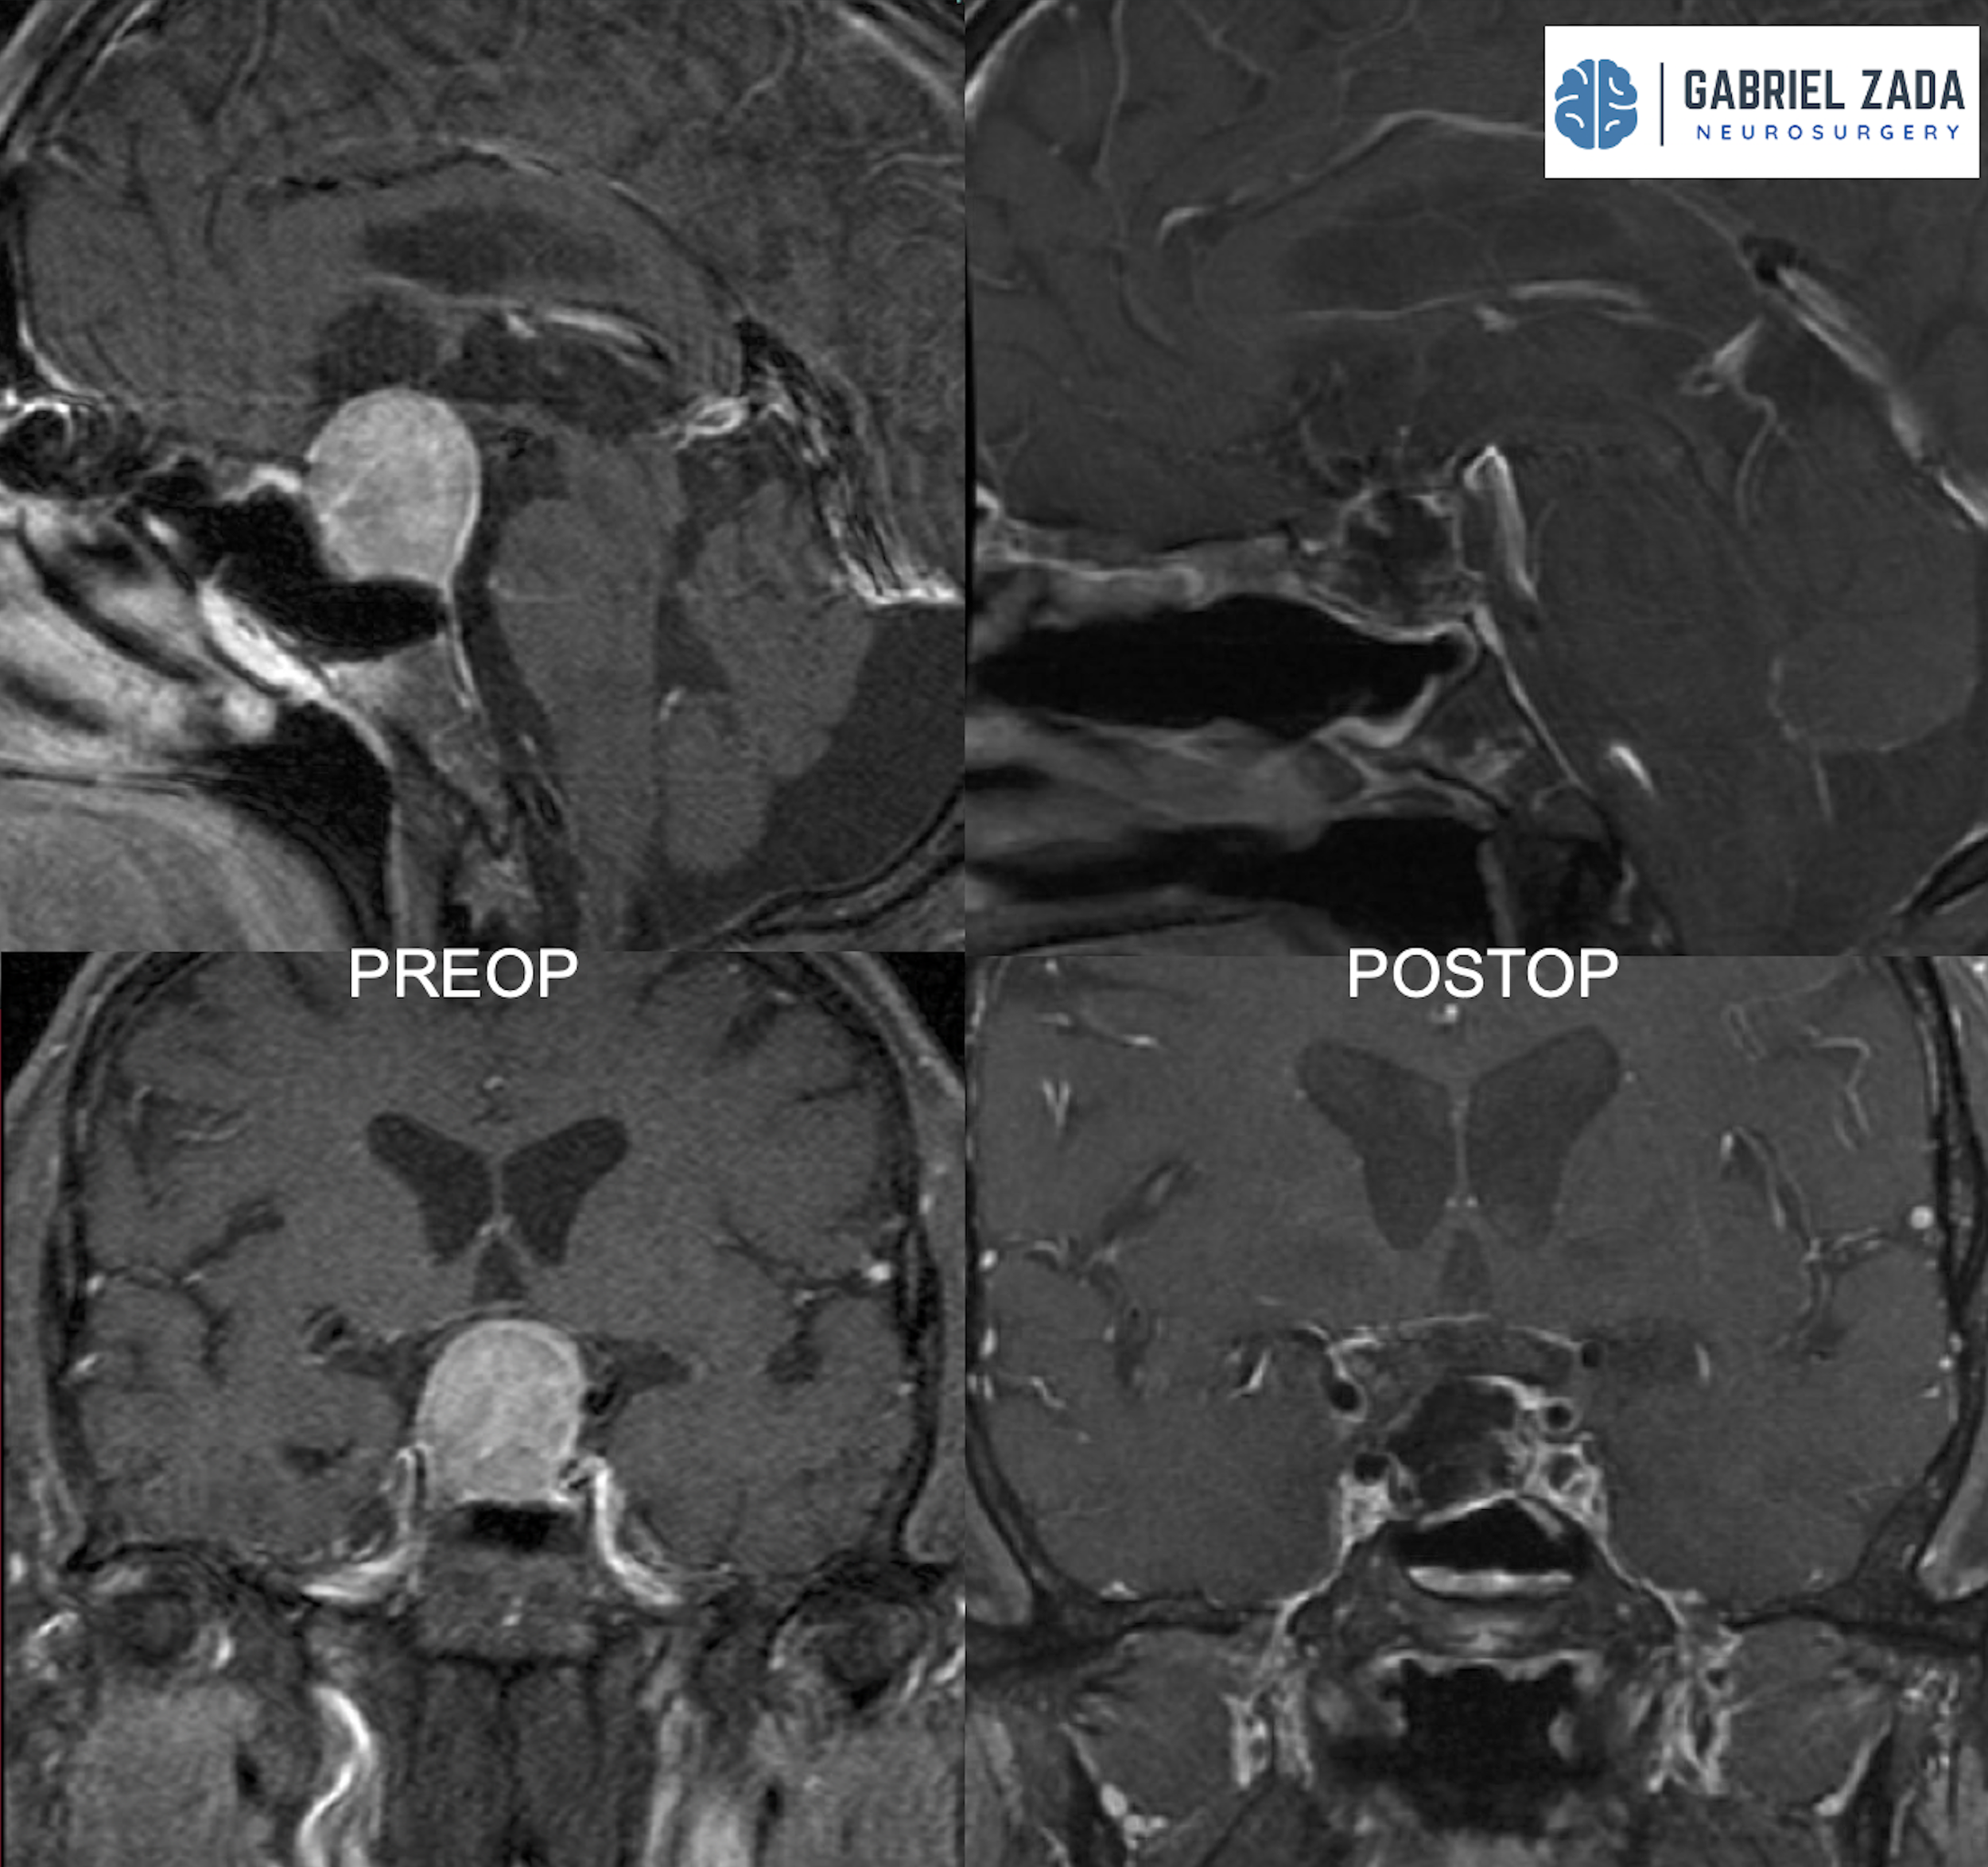

Explore this comprehensive gallery featuring pre‑ and post‑operative imaging of patients with skull‑base tumors treated by Gabriel Zada, MD, MS, FAANS, FACS. These cases highlight Dr. Zada’s expertise in advanced neurosurgical techniques and outcomes.

*Representative cases shown for educational purposes. All images de-identified. Individual results vary.